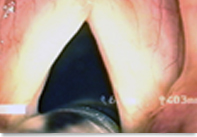

예송음성센터 김형태원장은 새로운 성대질환의 치료방법으로 최근 아시아에서는 처음으로 도입하여 시행한 "후두내시경 펄스다이레이져 성대수술" 방법에 대한 치료의 유용성 및 치료결과에 대한 임상연구결과를 "제 12차 대…